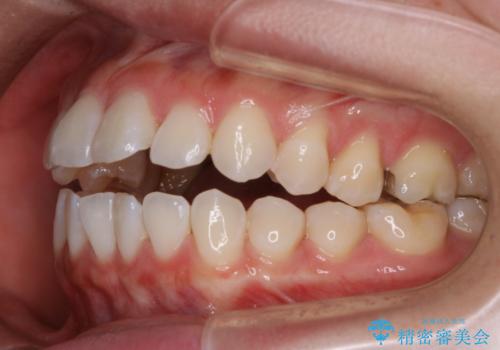

前歯で噛めない:オープンバイト(開咬)を非抜歯インビザラインで治療

- 上下の歯が噛んでいないことを気にしてご相談にいらした方です。

舌癖も認められたため、舌のトレーニングも併せて行い、矯正治療の効率化を図ると同時に後戻りのリスクを最小限に抑えるようにしました。

オープンバイトの方への治療は、通常抜歯を行いワイヤーによる矯正治療を行うことが多いですが、今回はインビザラインの特性を生かし、非抜歯にて綺麗な歯並びを作ることが出来ました。

舌癖がある方は、歯を内側から押し出す力が日常的に働くため、矯正治療後も歯と歯の隙間が開いてしまうなどの後戻りのリスクが高いことが知られています。舌の正しいポジショニングやお口周りの筋肉のトレーニングを行うことで後戻りのリスクを減らすことが可能です。